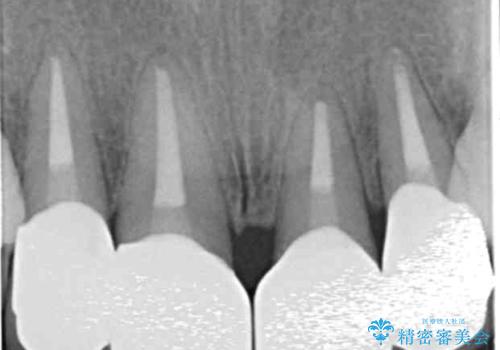

- 前歯のぐらつき、見た目の改善を希望され来院されました。

ぐらつきのある歯は、破折が認められ、その他前歯も不十分な根管治療や不適合なクラウン、レジン修復により審美障害が起きています。

問題を一つづつ丁寧に解決し、前歯の審美性の改善を計画します。